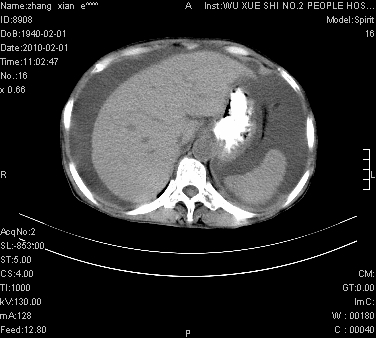

标题: CT24434:70岁 女 腹胀,腹水原因待查 [打印本页]

标题: CT24434:70岁 女 腹胀,腹水原因待查

大量腹水,脾脏囊性占位,子宫颈占位,右侧腹股沟淋巴结肿大,建议+c,先查妇科。

大量腹水,脾囊肿可能性大,建议增强

腹盆腔大量积液,子宫增大,子宫颈增大外形不规则,内见低密度影,膀胱后壁显示不清,右腹股沟肿大淋巴结,脾脏囊性占位,子宫颈占位,子宫颈癌?建议增强。

大量腹水,右肾、脾囊肿可能性大          考虑左侧附件区占位,建议增强